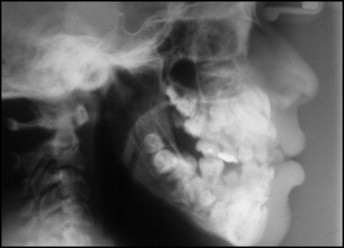

Qua khám trong miệng, các bác sĩ ghi nhận chỉ có 5 răng vĩnh viễn đã mọc. Trong khi đó, các răng sữa vẫn còn tồn tại khá nhiều. Nhằm đánh giá toàn diện hơn tình trạng răng miệng của bệnh nhi, các bác sĩ đã chỉ định chụp phim toàn cảnh và phim sọ nghiêng. Kết quả phim cho thấy một bất thường nghiêm trọng: sự hiện diện của rất nhiều răng thừa.

Hình chụp X-quang của bệnh nhi

Cụ thể, kết quả chụp đã cho thấy bệnh nhân có tổng cộng 81 chiếc răng, bao gồm: 18 răng sữa, 32 răng vĩnh viễn và 31 răng thừa. Các hình ảnh cũng cho thấy nhiều răng có hình thể bất thường khiến việc phân biệt giữa răng thường và răng thừa trở nên vô cùng khó khăn.